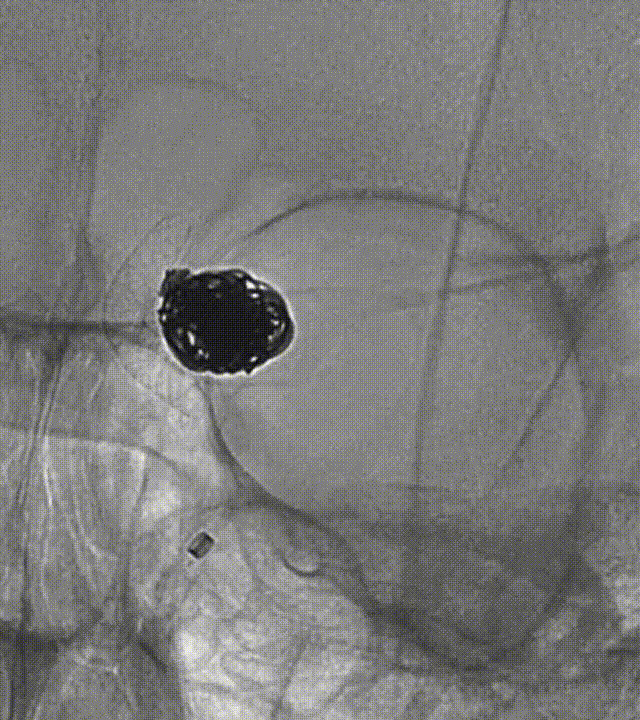

释放后造影:Lattice头端打开稍欠满意,中段打开完好。

支架后处理:微导丝按摩支架远近端辅助支架进一步打开。

按摩后支架贴合良好,支架头端位于颈内动脉分叉部近端(白箭头)。

多角度造影支架整体贴合好,支架远端位于颈内动脉分叉处近端,近端位于眼动脉开口以远,未覆盖眼动脉。